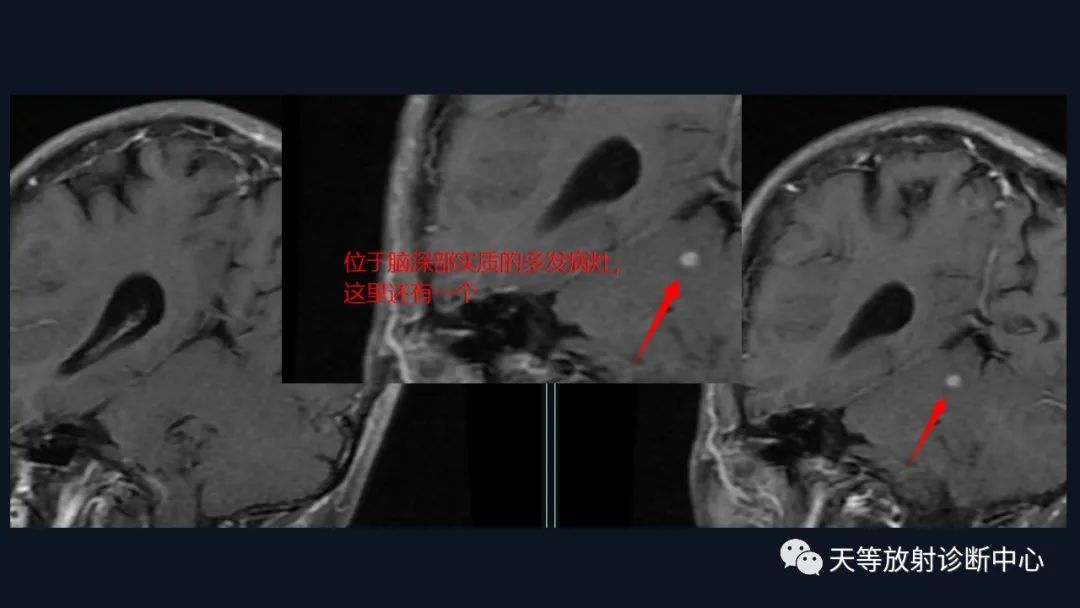

4、多发

结合颈部、胸廓入口区及腋窝多发淋巴结肿大并相互融合。

综合考虑淋巴瘤